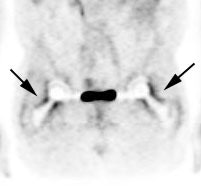

Peri-prosthetic activity: The patient below had bilateral hip prostheses. Note how the periprosthetic tracer uptake (black arrows) becomes less conspicuous on the non-attenuation corrected images (right). |

|